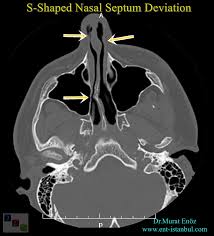

A deviated septum occurs when the thin wall (nasal septum) between your nasal passages is displaced to one side. One type of injury to the. Some of its causes, like cocaine use and certain surgical procedures, such as septoplasty, increase its incidence. The level of improvement you can expect with surgery depends on the severity of your deviation. The nasal septum is supported by two bones, the ethmoid bone on top and the vomer bone sitting behind the cartilage and ethmoid bone. The nasal septum is the bone and cartilage in the nose that separates the nasal cavity into the two nostrils. It is depressed by the depressor septi nasi muscle. It is depressed by the depressor septi nasi muscle.

In your case there's a little deviation to 1side or the other. Nasal septum perforation is a condition that affects the nose. The bony part is formed almost entirely by: Acquired nasal septal abnormalities may be caused by trauma, infection, toxicity, inflammation, or tumors. Slow or obstruct the flow of air on one side or the other. If your wall is way off, you have. Typically, it sits at the center and divides the nostrils evenly. However, in some people, this isn't the case.

Slow or obstruct the flow of air on one side or the other. The nasal septum is the median osseocartilaginous partition between the two halves of the nasal cavity. In your case there's a little deviation to 1side or the other. Weltgrößter piercingshop mit über 80.000 produkten. However, it's also associated with a high risk of complications. During septoplasty, your nasal septum is straightened and repositioned in the center of your nose. The bony part is formed almost entirely by: It extends from the nares anteriorly to the choanae posteriorly and is covered by squamous epithelium. It is depressed by the depressor septi nasi muscle. The septum divides the nasal cavity (inside your nose) into a right and left side. Nasal septum perforation is a condition that affects the nose. The tissue that surrounds the septum fluctuates in order to heat, humidify, and purify air as it enters our airways. The nasal septum is a wall made of cartilage and connective tissue that separates the nasal passages.